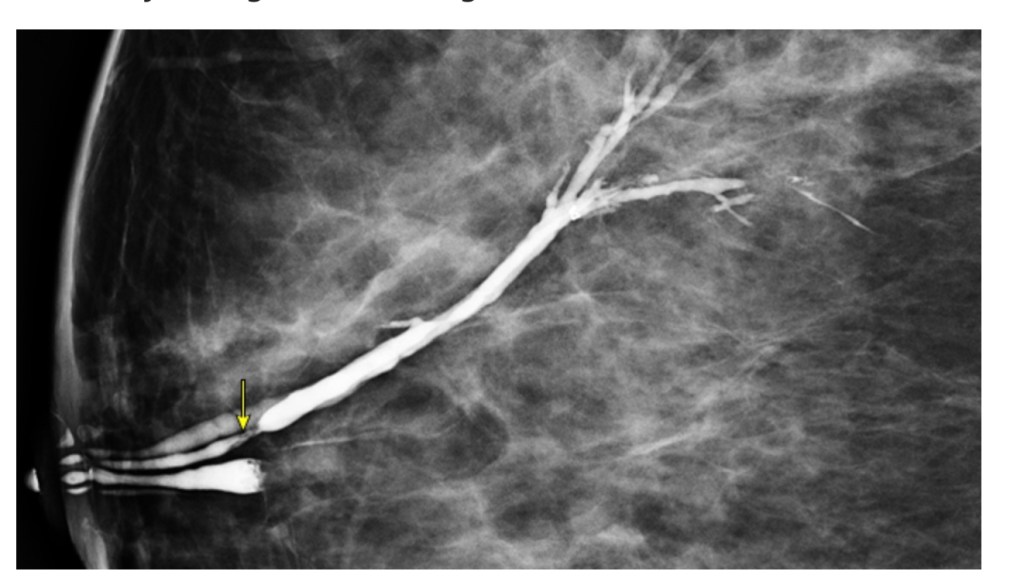

- At institutions where it is available, galactography (ductography) or ductoscopy may also be performed to evaluate pathologic nipple discharge in patients who have negative mammogram and ultrasound

- However, these studies are less widely available, and any lesions identified are not accessible to needle biopsy and, therefore, require surgical excision with the duct

- Galactography is a delicate, technically challenging study that can only be performed if the nipple discharge is reproducible on physical examination

- During a galactography examination, the discharging nipple orifice is cannulated and injected with a small amount of contrast material, which allows a subsequent mammogram to visualize a filling defect

- The intraductal lesion will appear as an intraductal filling defect, a complete ductal obstruction, or a wall irregularity

- Although peripheral intraductal masses have been reported, the vast majority of intraductal masses are centrally located, near, or immediately deep to the nipple-areolar complex

- In one study, galactography was associated with a sensitivity of 76% and specificity of 11%

- The positive predictive value of galactography in this series was 19%

- A successful galactography may help locate the lesion, which can aid the surgeon in more precisely localizing the proper area at the time of surgery, thereby limiting the amount of tissue excised

- However, the absence of a lesion on galactogram does not exclude a cancer

- Galactography should not be performed in patients with mastitis or a breast abscess, as it could worsen the inflammation

- Galactography can cause mastitis if too much contrast material is injected or if too much pressure is used during injection, resulting in perforation of the duct and extravasation of contrast material